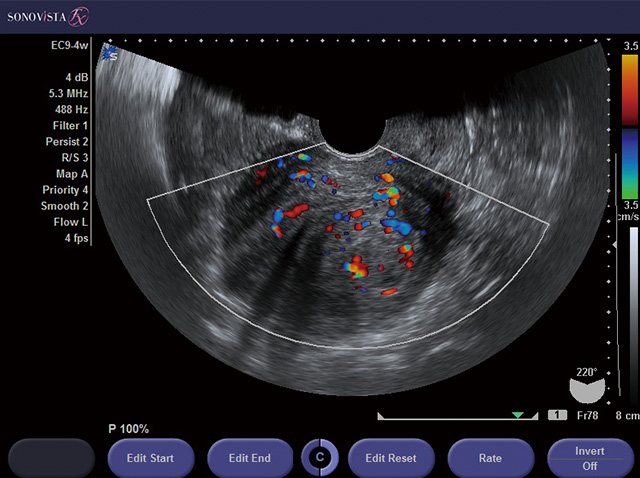

子宮筋腫、子宮内膜症(良性腫瘍疾患)について 患者さんへ 東京

【子宮筋腫】社会医療法人社団 カレスサッポロ 時計台記念病院 女性総合診療チーム

子宮筋腫が心配な方|日本医科大学付属病院